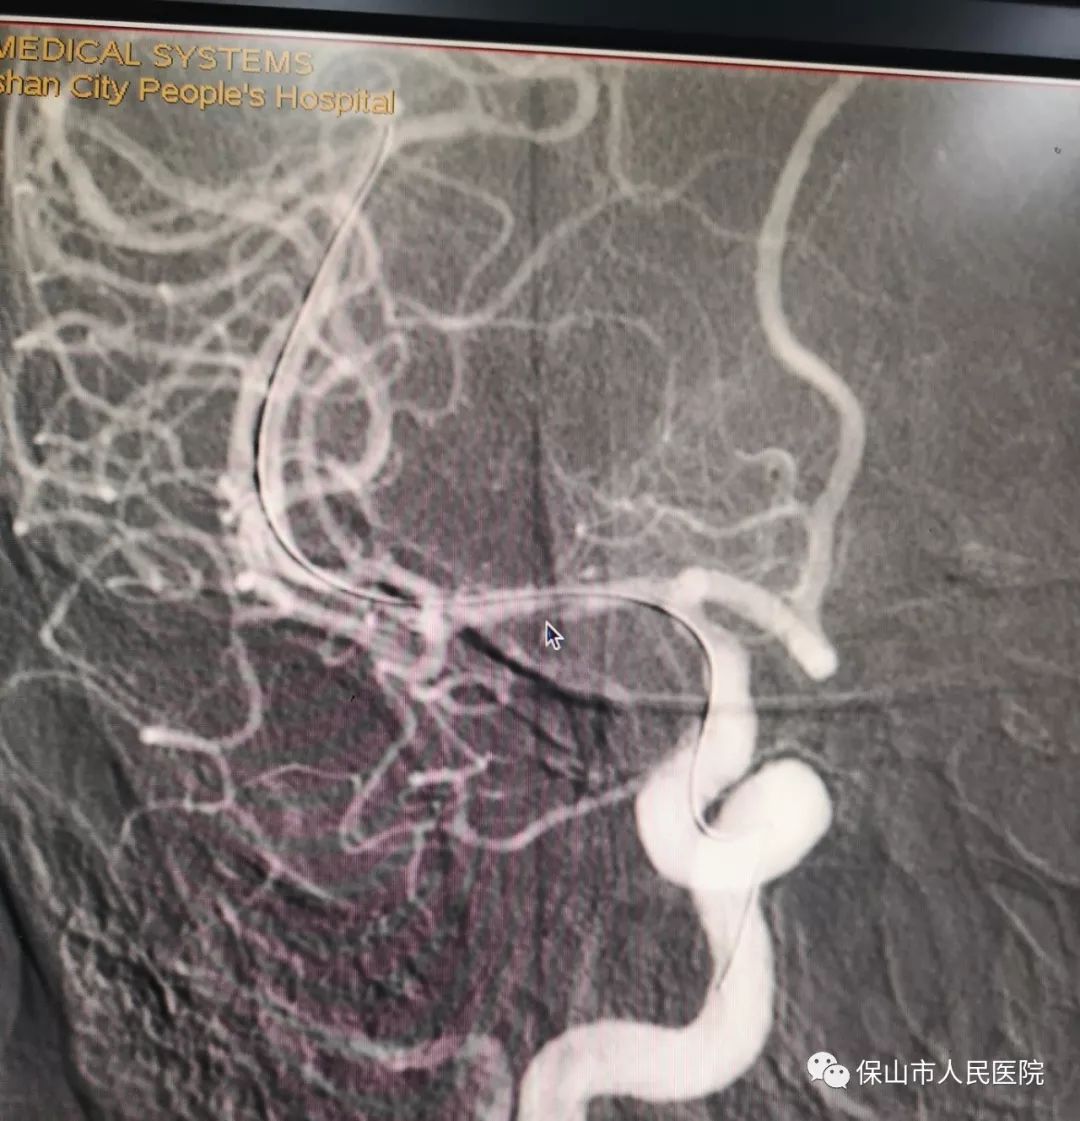

支架植入完成後,再次造影,可以看到,不僅(jin) 狹窄部位支撐開了,而且狹窄部位後麵的血管裏的血流速度也比手術前增加了。狹窄部位撐開,血流速度恢複,兩(liang) 個(ge) 條件都滿足了,手術也就圓滿結束了。

此次手術的成功,也標誌著kaiyun体育官方网站神經介入治療技術再一次進入到一個(ge) 新的高度。其中椎動脈支架植入術在kaiyun体育官方网站已並非第一次開展,早在今年3月,醫院就已完成過2例顱外動脈支架植入術,包括1例椎動脈狹窄支架植入術和1例頸動脈狹窄支架植入術。此次手術在原來的基礎上再次攻克了顱內(nei) 血管支架植入術的難題,隨著顱內(nei) 外血管支架植入術的開展,kaiyun体育官方网站將更好的服務於(yu) 有這方麵治療需求的患者,讓患者早日告別困擾多年的痛苦。